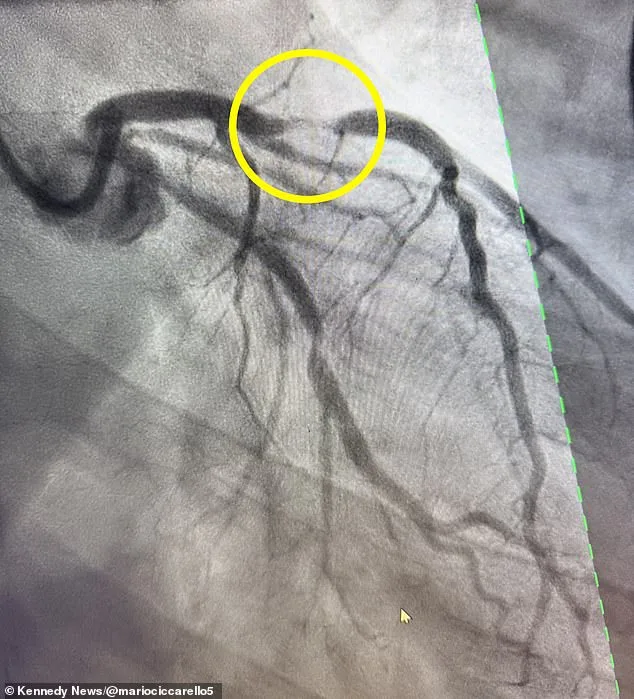

When the pain became unbearable, Ciccarello confronted James, insisting this was no longer a joke. The couple rushed to the hospital, where scans revealed a 95% blockage in his left anterior descending (LAD) artery—a condition known as a 'widow-maker' heart attack. This type of event is named for its high fatality rate, with only about 12% of patients surviving due to the catastrophic damage it inflicts on the heart's pumping chamber. Doctors explained that the LAD artery supplies over half of the heart's blood, making its blockage a medical emergency. While such attacks are more common in men in their 40s, women over 50 are also at heightened risk. Ciccarello's case is part of a troubling trend: heart attacks among young, seemingly healthy individuals are rising. In 2019, 0.3% of adults under 40 had experienced a heart attack, but by 2023, that number had jumped to 0.5%—a 66% increase in just four years. Now, one in five heart attack patients is under 40, a shift that has stunned medical professionals.

Experts are scrambling to understand why this is happening. While traditional risk factors like obesity and poor diet play a role, many young patients, including Ciccarello, have no clear explanation for their condition. Doctors suspect a genetic predisposition may be at work, though tests are ongoing to pinpoint the exact cause. Environmental factors, such as pollution, and delayed medical screenings are also under scrutiny. 'This is not just about lifestyle choices,' said one cardiologist involved in Ciccarello's case. 'There's something in the environment or our genetics that we're not fully understanding yet.' Despite the grim statistics, Ciccarello's story has a silver lining. Emergency interventions, including the placement of two stents to restore blood flow, saved his life. Now on blood thinners and undergoing genetic testing, he is using social media to warn others about the subtle signs of a heart attack: chest pain, shortness of breath, dizziness, nausea, fatigue, and lightheadedness. 'I could have died,' he said. 'Every minute you wait, more damage is done. I wish I had gone to the hospital sooner.'